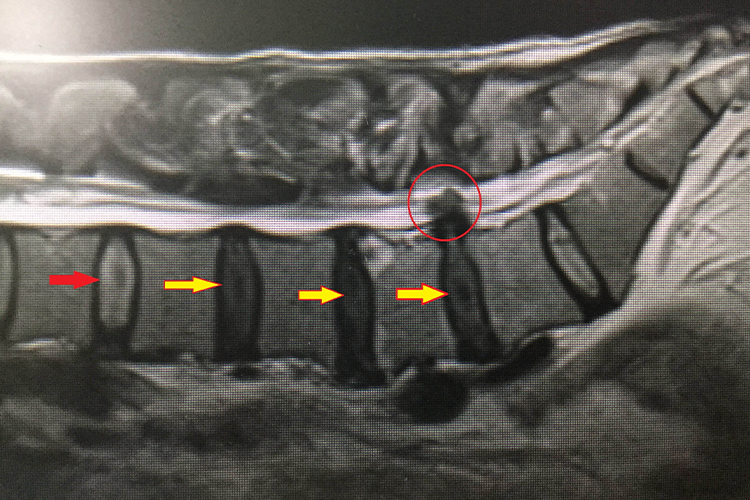

腰椎间盘突出症的患者进行X线、CT等影像学检查时,可见腰椎生理前凸减少或消失,椎间隙狭窄,以及腰椎间盘变形突出、硬脊膜囊受压变形、硬膜外脂肪移位、硬膜外间隙中软组织密度影及神经根鞘受压移位等现象。